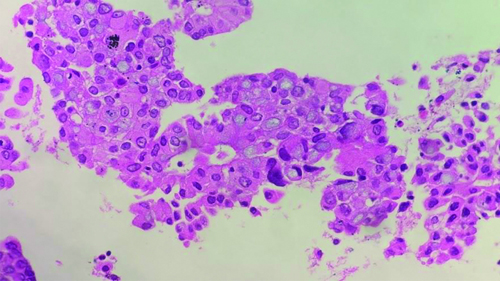

Endobronchial Ultrasound-guided Transbronchial Needle Aspiration (EBUS-TBNA) with a total of 7 passes was done. The aspirate and bronchial wash were reported as suspicious for malignant cells [Table/Fig-4a]. The EBUS-TBNA core [Table/Fig-4b] and endobronchial biopsies were received as multiple very tiny grey-white to grey-brown soft-tissue bits altogether aggregating to 0.5 cc. Histopathological analysis of the endobronchial biopsy [Table/Fig-5] revealed the diagnosis of lung adenocarcinoma with SRC morphology characterised by abundant intracellular mucin accumulation and a crescentic nucleus displaced toward one end of the cell. This was confirmed by IHC, the tumour cells showed positivity for markers CK7 [Table/Fig-6] and TTF-1 [Table/Fig-7]. Further, the tumour was positive for ALK [Table/Fig-8] gene rearrangements and negative for ROS proto-oncogene1 (ROS1) fusion by IHC. Epidermal Growth Factor Receptor (EGFR) mutational analysis was done by Polymerase Chain Reaction (PCR) and no mutation of the EGFR gene was detected.

Endobronchial biopsy showing atypical cell clusters, few with intracytoplasmic mucin, resembling Signet Ring Cells (SRC), along with bronchial epithelial cells nests (H&E stain x200).